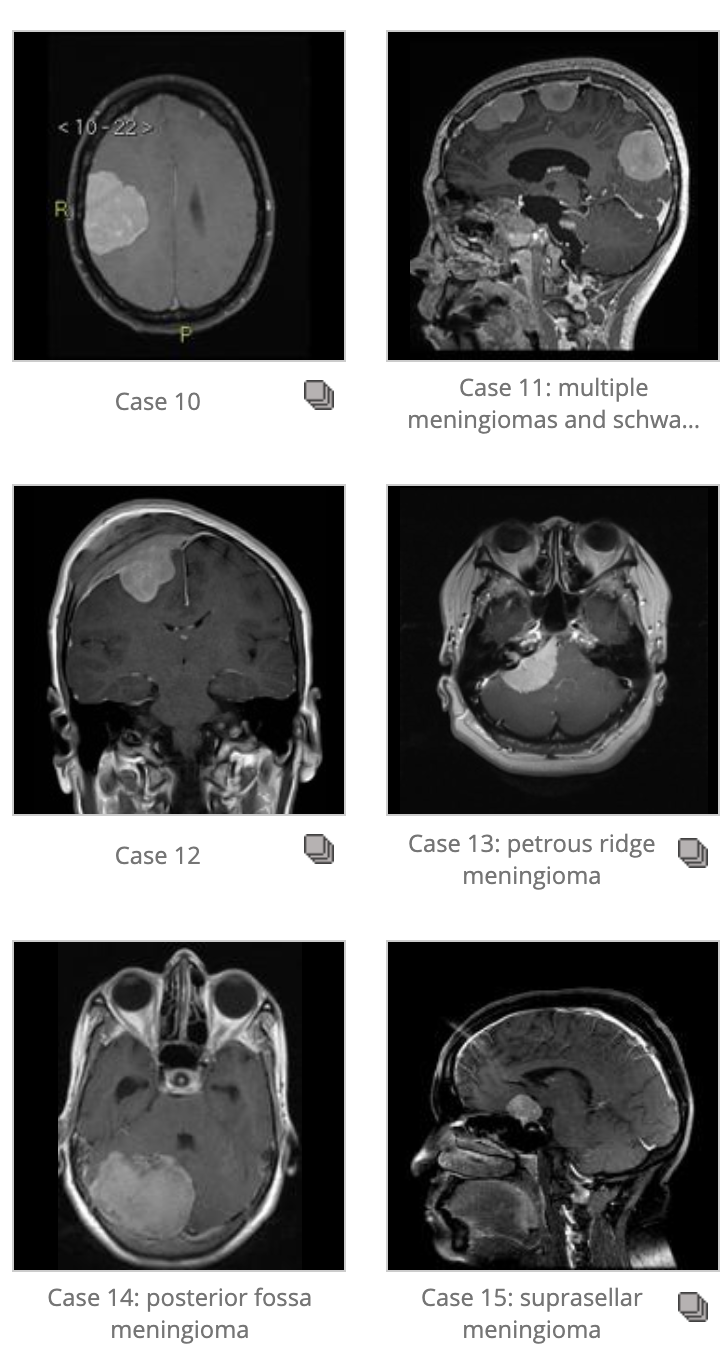

Meningiomas